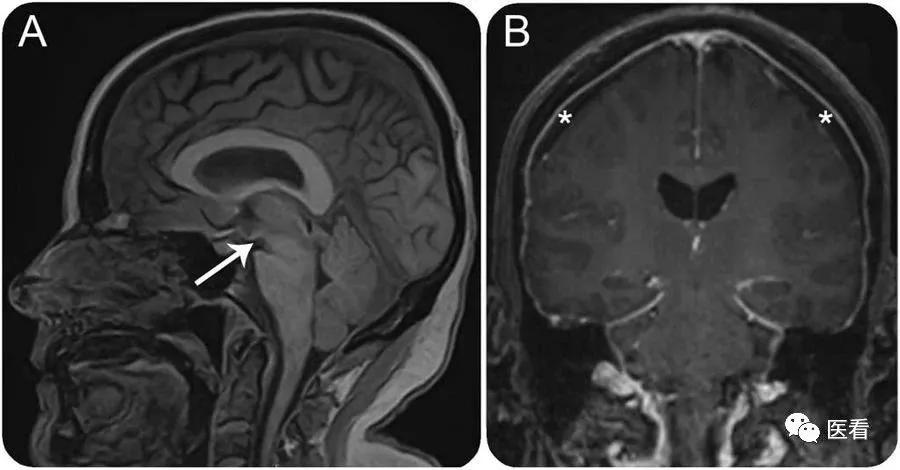

增强检查

要求:禁食3-4小时

不管是CT增强还是MRI增强,都需要空腹至少3-4小时,平扫检查则不需空腹(腹部检查除外)。

增强都需要注射造影剂,空腹是为了避免造影剂对胃肠道的刺激导致呕吐等现象影响检查过程。

腹部检查

要求:禁食6-8小时

最特殊的是腹部的检查, CT腹部平扫无需空腹,CT增强则需要空腹,MRI腹部无论平扫还是增强一律空腹,避免食物残渣对检查结果的干扰。同时去检查前最好带上一定量的水(500ml—100ml),根据检查需要在医生的指导下饮用。